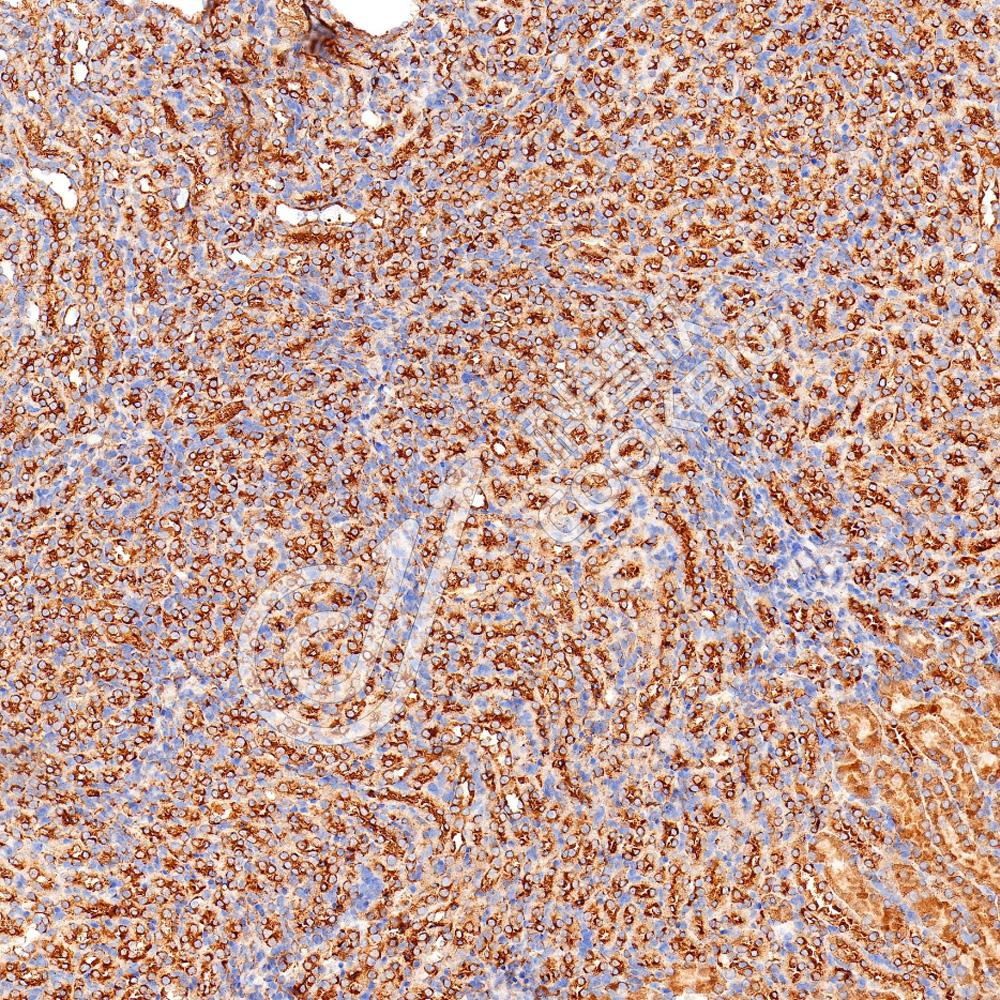

IHC检测Keap1蛋白(货号 K547541).

样品: 人肾, 4%多聚甲醛 (货号KSG1101) 固定12-24小时.

抗原修复: Tris-EDTA抗原修复液(pH 9.0) (货号KSG1203), 水浴100℃, 25分钟.

—抗: 1: 200稀释, 4℃ 孵育过夜.

二抗: S-vision免疫组化多聚二抗(山羊抗兔),即用型 (货号KB3906), 室温孵育20分钟.